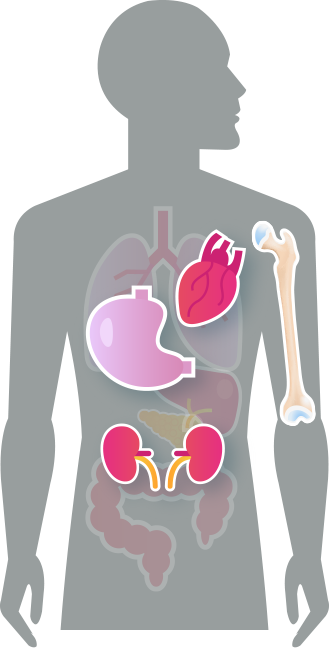

나트륨 과잉이 초래하는 질병

고혈압

혈관 내 삼투압이 상승하면서 혈관 내부 압력이 높아져 혈압을 상승 심장병/뇌졸증

고혈압으로 인해 심장혈관과 뇌혈관의 동맥경화를 유발 위암

나트륨이 위 점막 손상을 촉진해 위염을 유발하고, 위암 발생을 높임 만성신부전증

전신 혈압이 높아져 신장의 사구체와 주변혈관이 손상돼 기능 저하 골다골증

소변으로 나트륨 배출이 증가할 때 칼슘도 함께 빠져나가 골감소증이나 골다공증 위험이 높아짐 비만

짠 맛을 중화하기 위한 탄산음료, 아이스크림 같은 단 음식의 욕구가 높아져 과체중, 폭식으로 이어짐